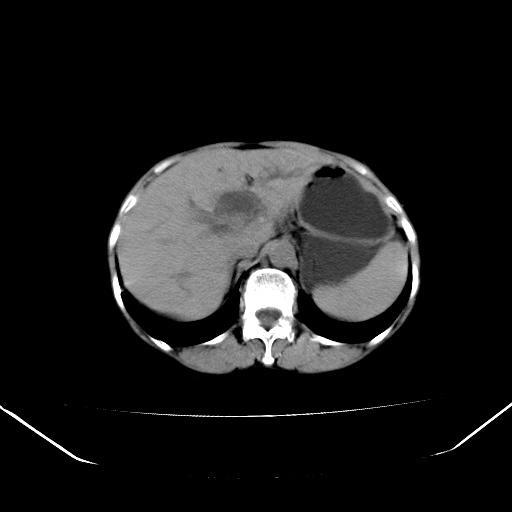

以下是引用jiangjing在2008-6-3 13:36:00的发言:[br]支持 胰头癌------肝内外胆管扩张,胰管扩张,胰头增大,增强见结节状轻度强化影,双管征明显

以下是引用卜一在2008-6-3 14:40:00的发言:[br]支持:胰头癌!(肝内外胆管扩张,胆囊高度扩张,胰管扩张,胰头增大,增强见结节状强化,明显低于胰腺强化密度,并明显见双管征)

以下是引用dyqct在2008-6-3 14:54:00的发言:[br]支持 胰头癌伴肝内外胆管扩张,胰管扩张,胰头增大,增强见结节状轻度强化影,双管征明显。肠系膜上静脉已受侵(已不能手术),建议离子植入治疗吧。